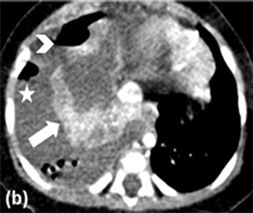

The thoracic X-Ray showed opaque right hemithorax, CT scan was required for better characterization, which objectified an abundant right pleural effusion with air-fluid level and millimetric air bubbles coming out of the collapsed lung, suspecting a broken congenital pulmonary airway malformation (Figure 1); the

Figure 1. Thoracic contrast CT in axial (a, b) and coronal (c) sections, showing an important right pleural effusion (asterisk) with air-fluid level (arrow head); the right lung parenchyma is collapsed (thick arrow) with adjacent air bubbles (thin arrow), raising the hypothesis of a broken congenital pulmonary airway malformation.

first malformations evoked were congenital pulmonary adenomatoid malformation and bronchopulmonary sequestration.